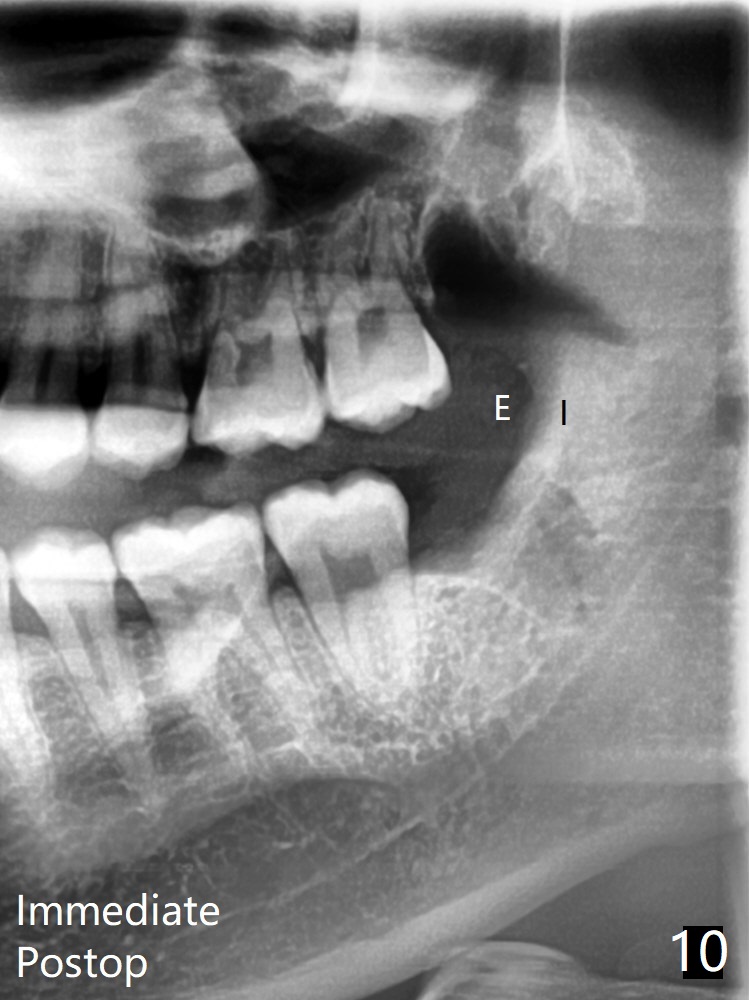

25岁男,特别紧张,要求先拔除左侧智齿(图一,十)。左下牙槽窝放置骨胶原塞。